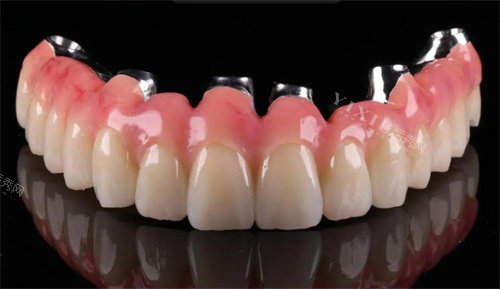

复合材料

复合材料是结合了金属和陶瓷优点的创新材质,通常采用金属底层和陶瓷表层的复合结构。这种设计既保留了金属的强度和支撑力,又实现了陶瓷的自然外观。复合材料能够满足患者对功能性和美观性的双重需求,应用范围较为广泛。然而,复合材料的制作工艺相对复杂,价格也处于中等偏上水平。对于既重视修复结果又关注美观的患者,复合材料提供了较为平衡的解决方案。